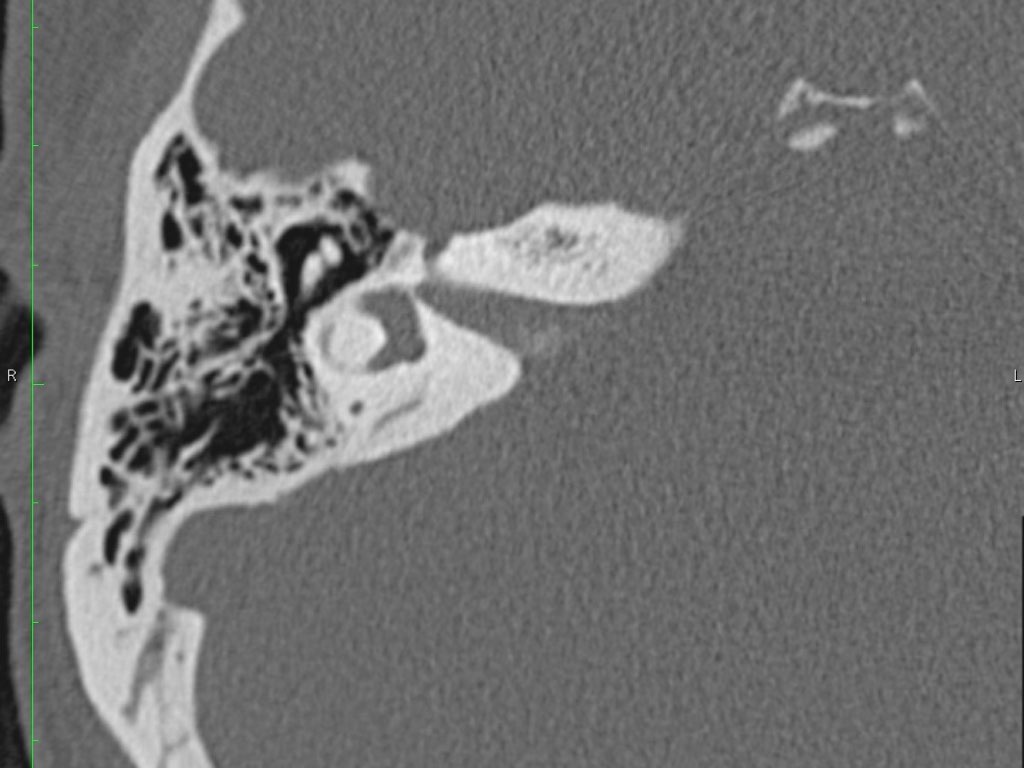

Thông qua ngách thượng nhĩ (aditus ad antrum), hòm nhĩ thông với hang chũm — một tế bào khí lớn nằm phía trên và phía sau hòm nhĩ — và thông với các tế bào khí chũm.

Hang bào chũm là một tế bào khí lớn nằm phía trên và phía sau hòm nhĩ, thông với hòm nhĩ qua ngách hang (aditus ad antrum).

Đoạn mê nhĩ của dây thần kinh mặt xuất phát từ ống tai trong, chạy gần như vuông góc với trục dài của xương đá, gập góc nhọn về phía trước để đến hạch gối (geniculate ganglion).

Tại hạch gối, dây thần kinh mặt tạo thành một khúc quặt hình chữ U (genu thứ nhất của dây thần kinh mặt) để chạy ra phía sau theo đoạn nhĩ dọc theo thành trong của thượng nhĩ.